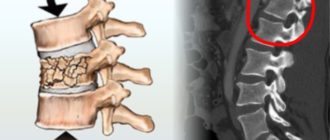

Давность перелома позвонка

Ортопед-травматолог

Перелом позвоночника (позвонка): основные симптомы и признаки перелома Для опорно-двигательного аппарата перелом позвоночника —